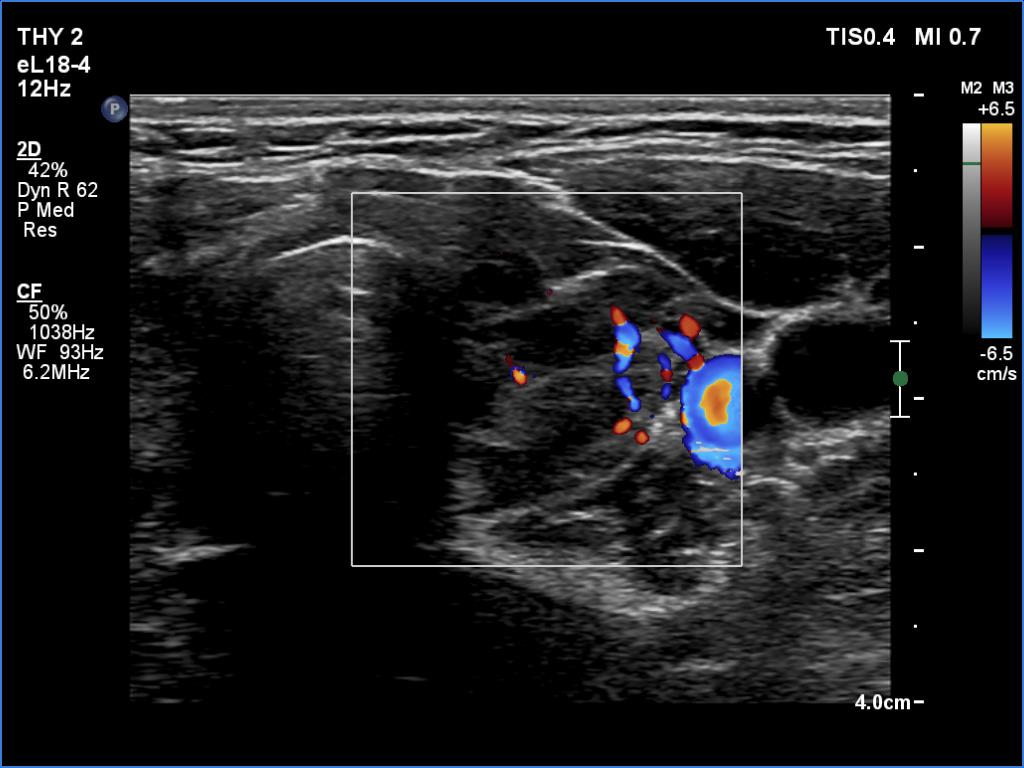

Left lobe, transverse view, color Doppler mode. This vascularity is not specific.